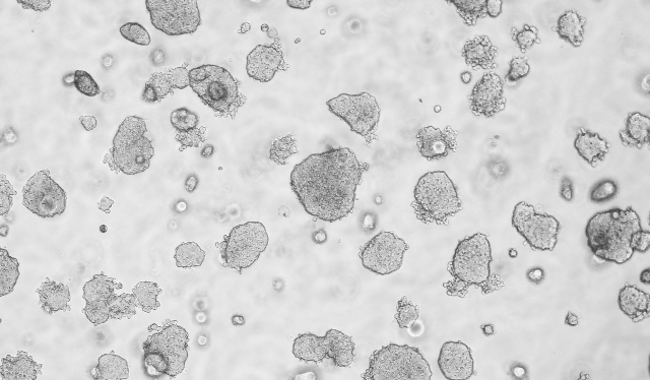

平板克隆形成圖像分析

平板克隆試驗是一種常用的測量細胞生長能力的技術(shù),從開始已知的細胞群體監(jiān)測菌落的形成。菌落的形成需要密集的分裂的原始細胞,所以在整個實驗的細胞或菌落的數(shù)量的量化是細胞的生長潛力的指標。因此,集落形成試驗已成為一種廣泛用于癌癥研究的方法來研究藥物和電離輻射療法對癌細胞增殖的影響。